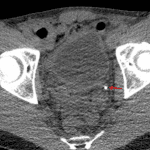

- 5 mm calcific density in the distal left ureter

- Mild left hydroureteronephrosis and perinephric stranding

- Small amount of fluid in the left perinephric space and left paracolic gutter

- Excretory phase images show evidence of forniceal rupture with pyelosinus reflux

- Obstructing ureteral calculus

Obstructing 5 mm distal left ureteral calculus with resultant mild left hydroureteronephrosis and evidence of forniceal rupture on excretory phase images.